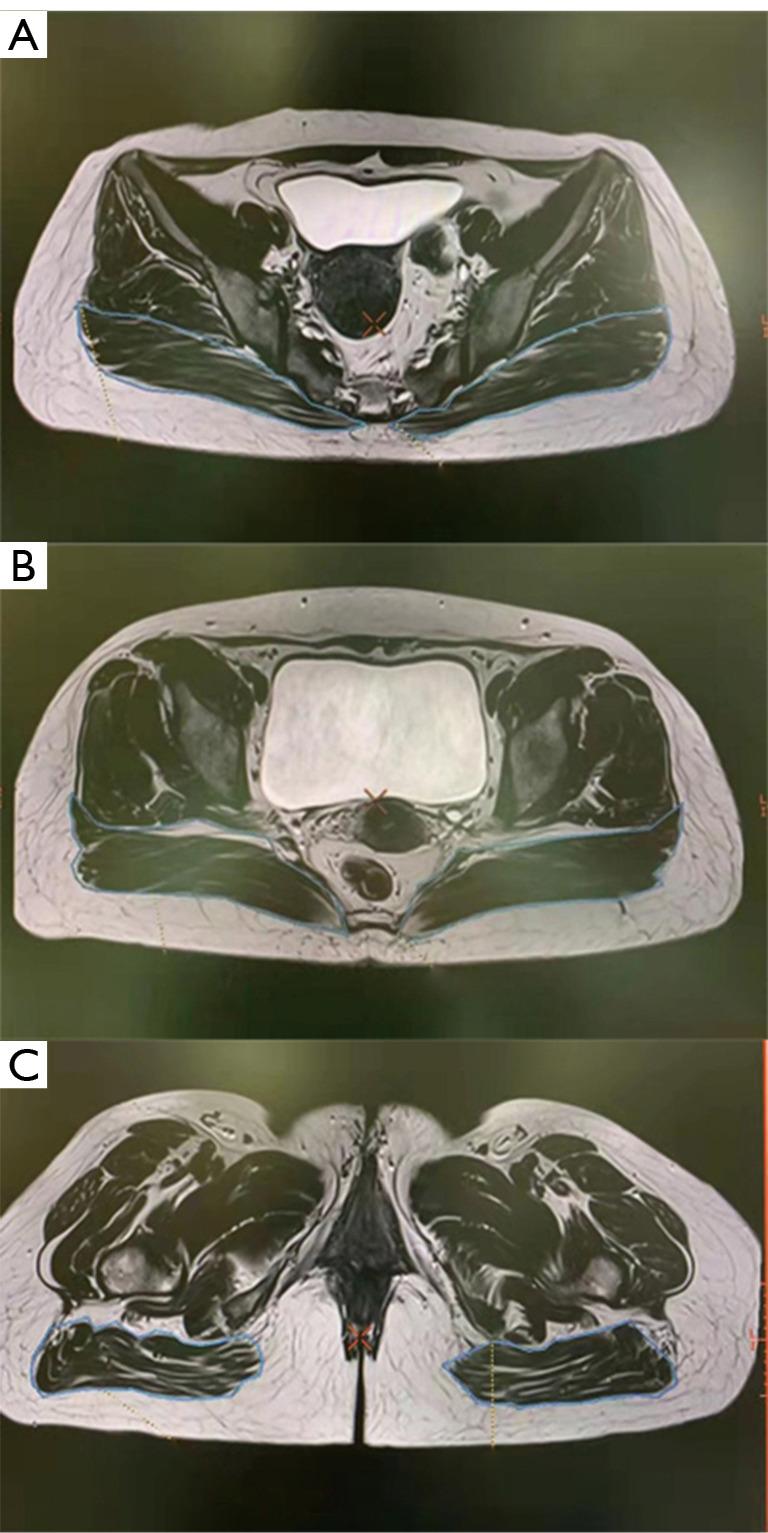

The objective of the current study was to retrospectively examine the morphological magnetic resonance imaging (MRI) characteristics of the gluteus maximus of buttock augmentation at levels of predetermined anatomic points.

The present study was a retrospective cross-sectional study. Adult women who underwent high-quality MRI scanning at Sun Yat-sen Memorial Hospital of Sun Yat-sen University from January 2018 to January 2021 were included in this work. The transverse MRI data measured at the inferior point of the sacroiliac joint, just above the femoral head, and at the ischial tuberosity were collected and statistically analyzed.

Fifty-two cases (104 sides of female gluteus maximus) were included in the final analysis. The A point (surgery starting point) were 54.4±6.34 mm, 54.91±5.57 mm, and 73.91±5.57 mm away from the posterior midline at the level of inferior point of the sacroiliac joint, just above the femoral head, and at the ischial tuberosity, respectively. Accordingly, the thickness of the muscle at these locations was 16.0±4.17 mm, 23.4±4.40 mm, and 24.6±7.58 mm, respectively. The diameter of the implant did not exceed 14.18±1.22 cm. In addition, the gluteus maximus at the lowest point of the sacroiliac joint and above the femoral head exhibited an arc structure, which needs to be tilted to the deep plane during separation.

本研究的目的是回顾性地研究在预定解剖点水平下用于臀部增大的臀大肌的形态磁共振成像(MRI)特征。

本研究为回顾性横断面研究。纳入了2018年1月至2021年1月在中山大学孙逸仙纪念医院接受高质量MRI扫描的成年女性。收集在骶髂关节下点、股骨头上方和坐骨结节处测量的横向MRI数据并进行统计分析。

最终分析纳入了52例(104侧女性臀大肌)。A点(手术起始点)在骶髂关节下点、股骨头上方和坐骨结节水平分别距离后正中线54.4±6.34mm、54.91±5.57mm和73.91±5.57mm。相应地,这些位置的肌肉厚度分别为16.0±4.17mm、23.4±4.40mm和24.6±7.58mm。植入物直径不超过14.18±1.22cm。此外,骶髂关节最低点和股骨头上方的臀大肌呈弧形结构,分离时需要向深层平面倾斜。